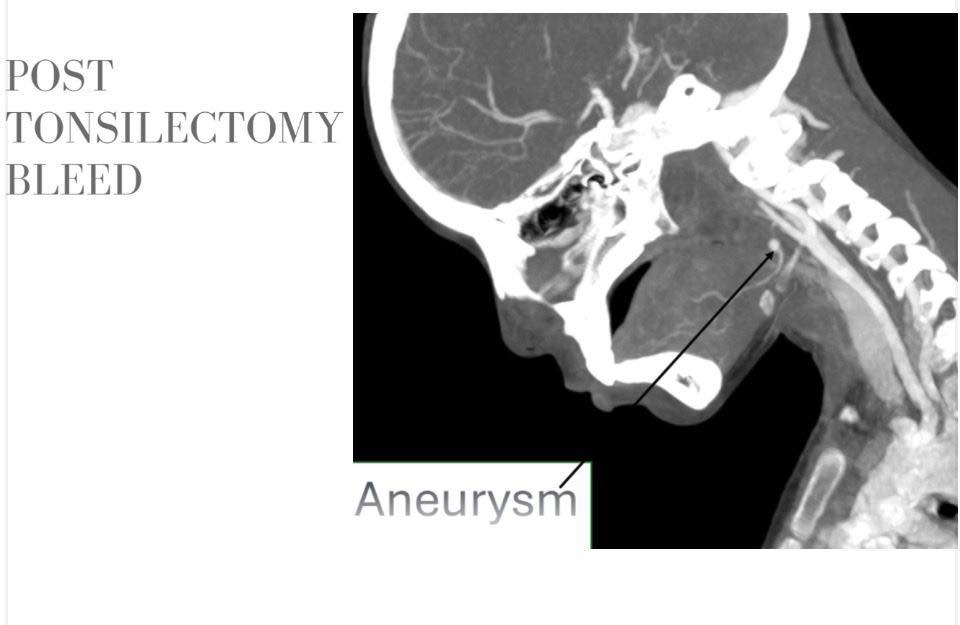

استقبلت مستشفيات سوهاج الجامعية، طفلة تبلغ من العمر 12 عامًا، تعاني من قيء دموي حاد، عقب خضوعها لعملية استئصال اللوزتين خارج المستشفى، أعقبها تدخل جراحي آخر للسيطرة على النزيف إلا أنه لم ينجح، ما استدعى نقلها إلى المستشفى الجامعي في حالة حرجة.

وأكد الدكتور حسان النعماني، رئيس الجامعة، أن سرعة التشخيص ودقة التدخل كانتا عاملين حاسمين في إنقاذ حياة الطفلة، مشيرًا إلى أن جاهزية مستشفيات سوهاج الجامعية والتكامل بين أقسامها المختلفة أسهما في التعامل الفوري مع الحالة وفق أحدث الأساليب العلاجية. وأضاف أن فريق الأشعة التداخلية أجرى الفحوصات والأشعات اللازمة فور وصول الطفلة، والتي كشفت عن وجود تمدد شرياني نازف بأحد الشرايين الرئيسية بالرقبة في جدار الحلق، ما تطلب تدخلاً عاجلاً عالي الدقة.

ومن جانبه، ذكر الدكتور احمد كمال، المدير التنفيذي للمستشفيات الجامعية، أنه تم تجهيز وحدة القسطرة على الفور، حيث نجح الفريق الطبي في غلق التمدد الشرياني باستخدام حلزونات دقيقة عبر القسطرة التداخلية، مما أسهم في السيطرة الكاملة على النزيف دون الحاجة إلى جراحة تقليدية، وتقليل احتمالات المضاعفات.